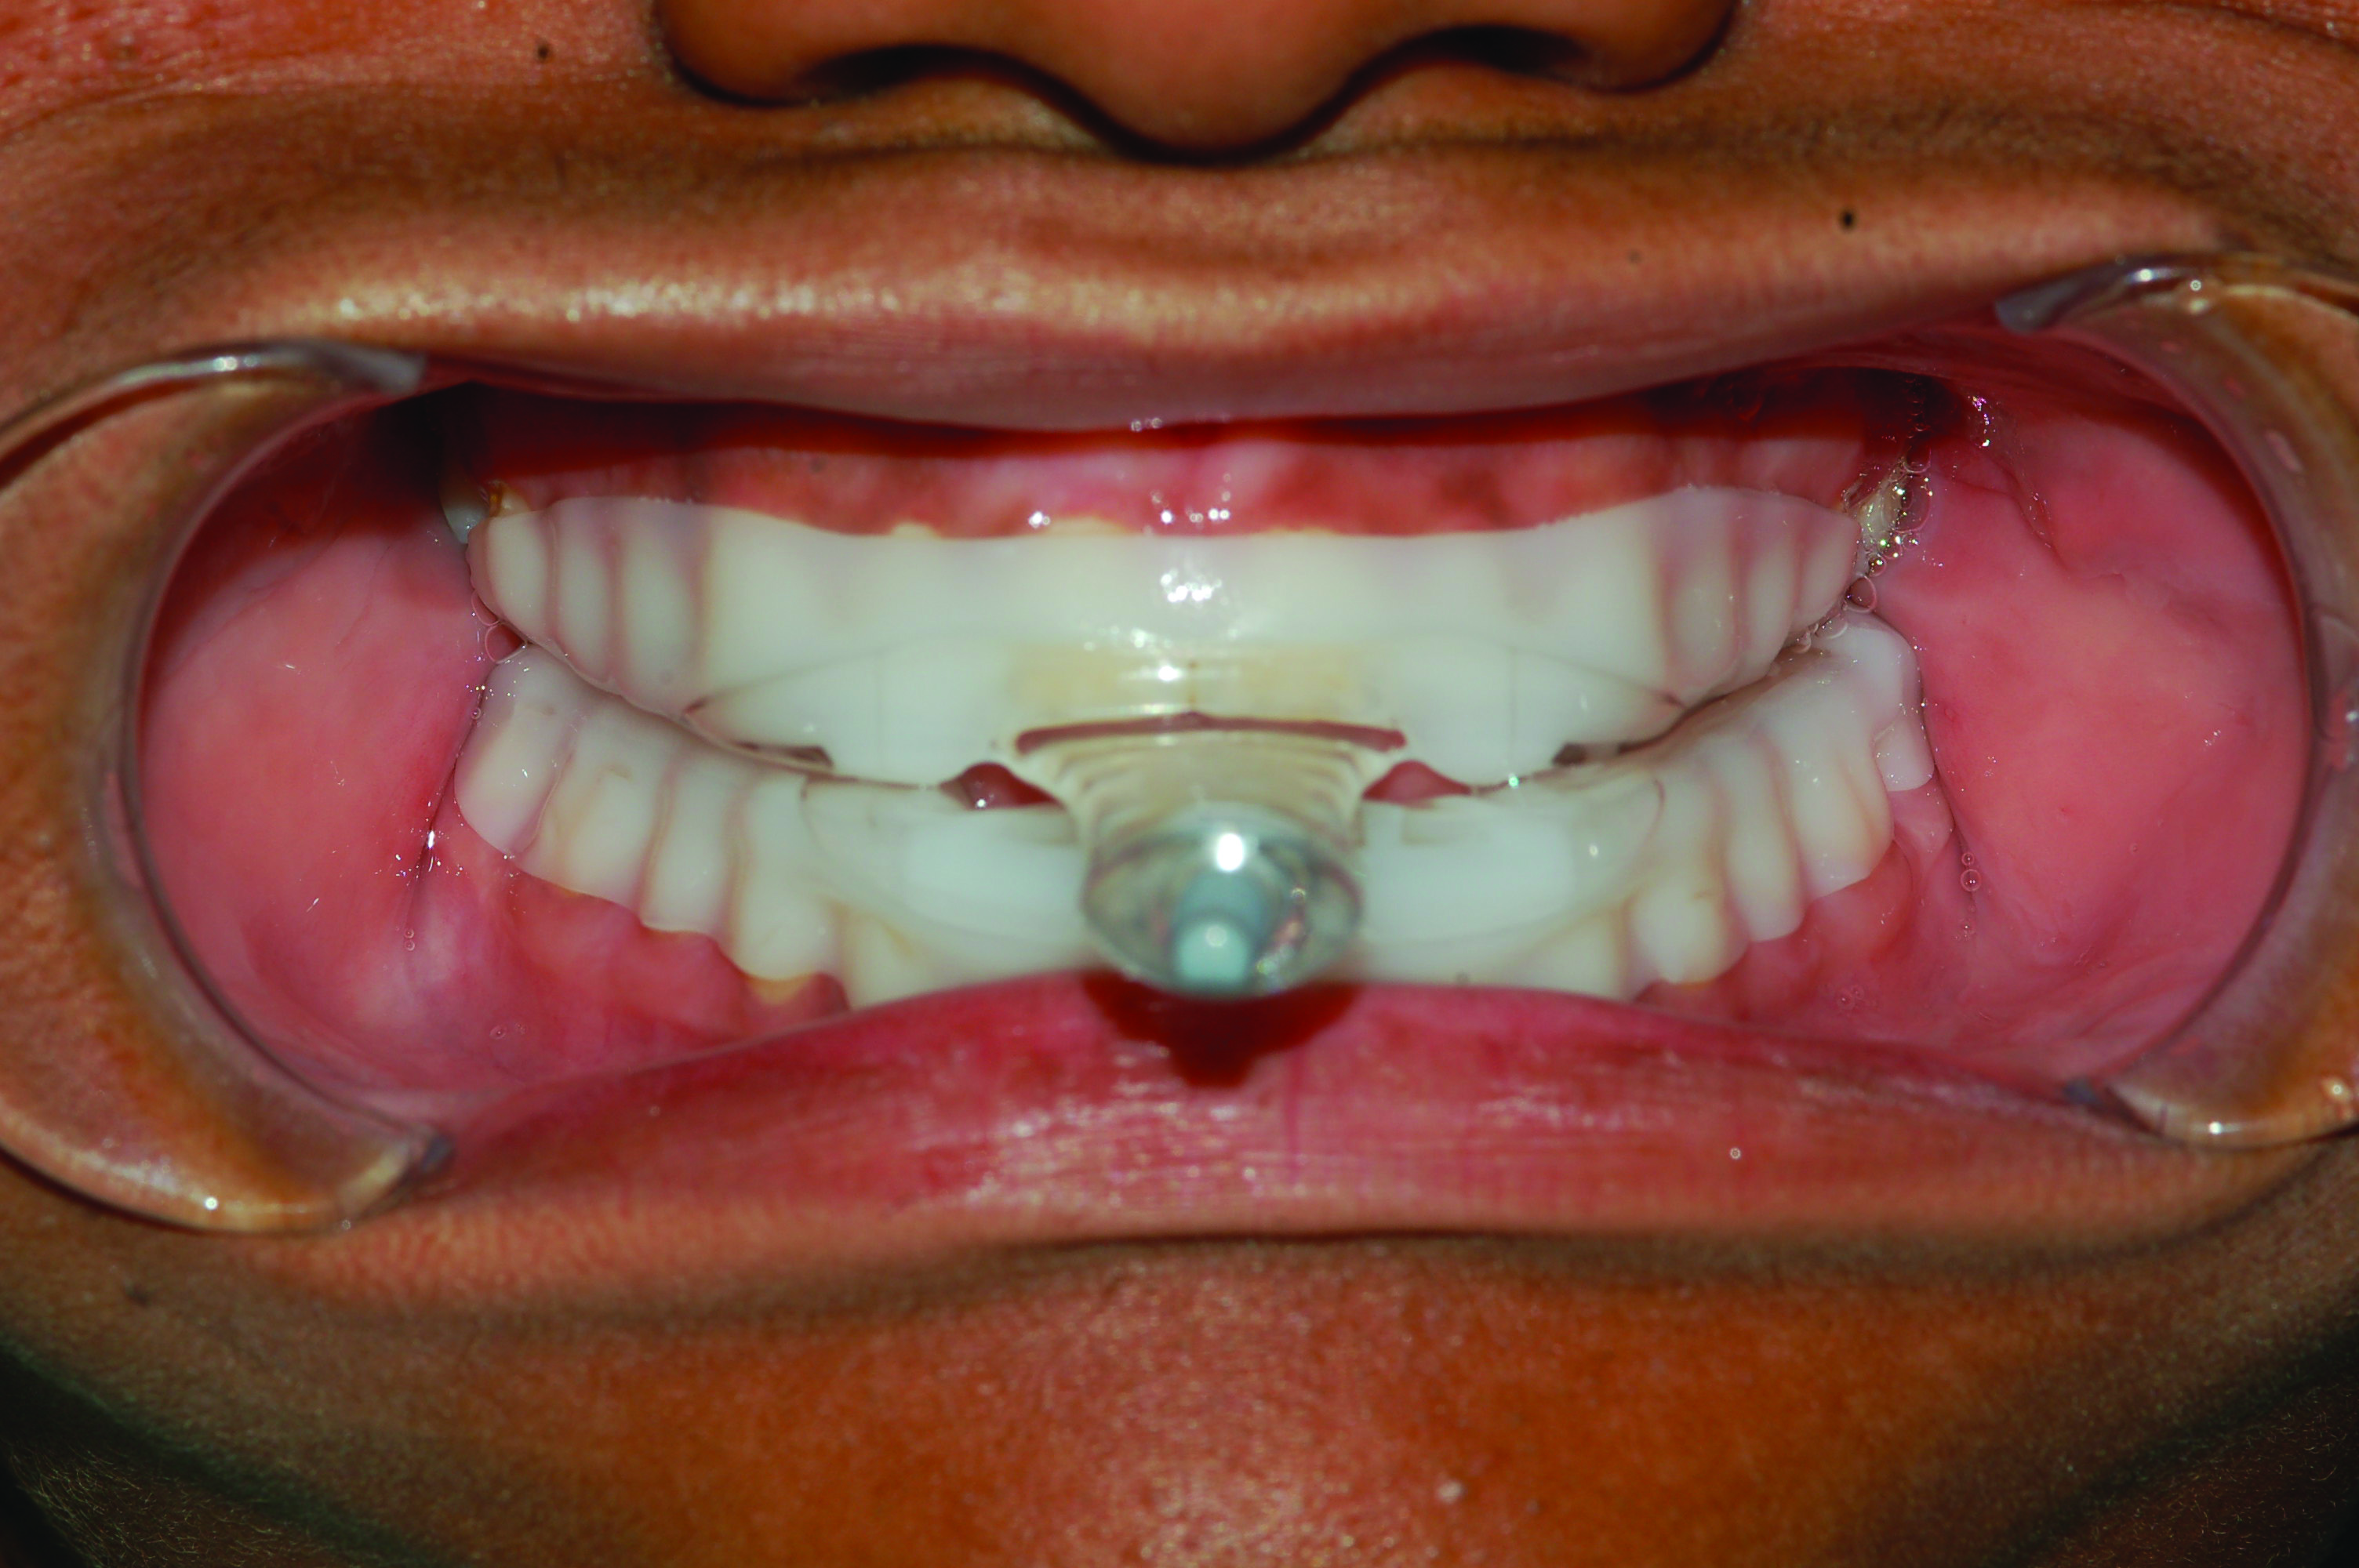

Fig 7. Development of posterior open bite. Photograph of male patient with teeth maximally intercuspated prior to treatment (AHI in supine position = 88.2 events/hr).

Figure 7

Fig 8. Photograph of teeth maximally intercuspated 10 months after patient began treatment with a MAD (TAP® appliance). With the jaw advanced 95% of maximum protrusion, the AHI in the supine position was reduced to 1.1 events/hr. A posterior open bite was observed on both sides of the dental arch.

Figure 8

Within the first few months of treatment, some patients report difficulty achieving a firm bite with the back teeth. The mechanism underlying the development of this posterior open bite is unclear but of intense interest. When observed early after the beginning of treatment, it may be due to changes in the TMJ soft tissue or in the masticatory muscles. Later in treatment, the development of a posterior open bite may reflect the inability to fully close due to premature contact of the anterior teeth (Figure 7 and Figure 8).11 Alternatively, some investigators have suggested an anterior bony repositioning of the mandible from its original position.12